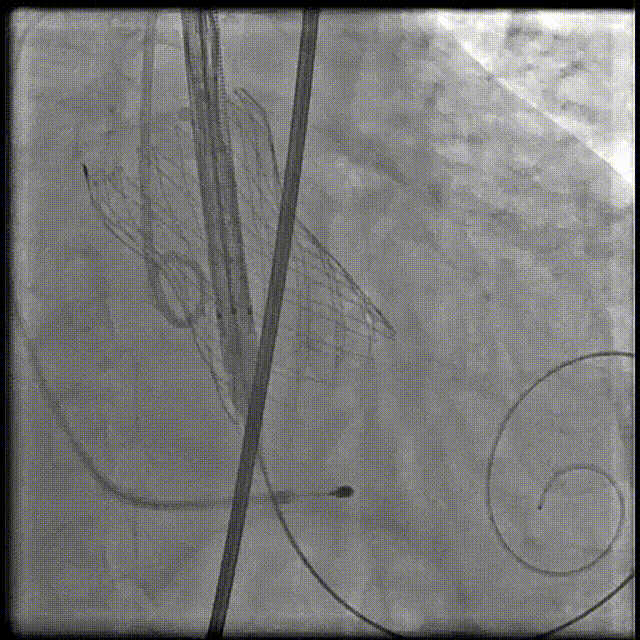

输送器柔顺过弓、跨瓣

瓣膜开始定位

第一个瓣膜释放

植入第二个瓣

最终造影:无反流